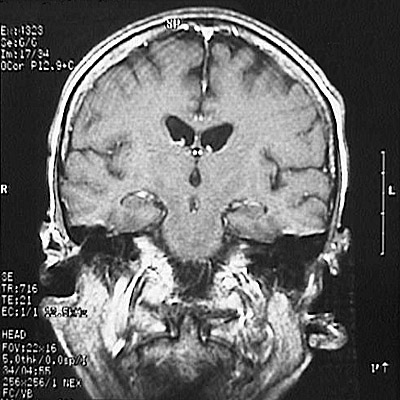

This is a normal coronal T1 weighted enhanced MRI scan demonstrating the frontal lobe and temporal lobe and hippocampus and thalamus and pons and lateral ventricle and third ventricle and superior sagittal sinus and corpus callosum.